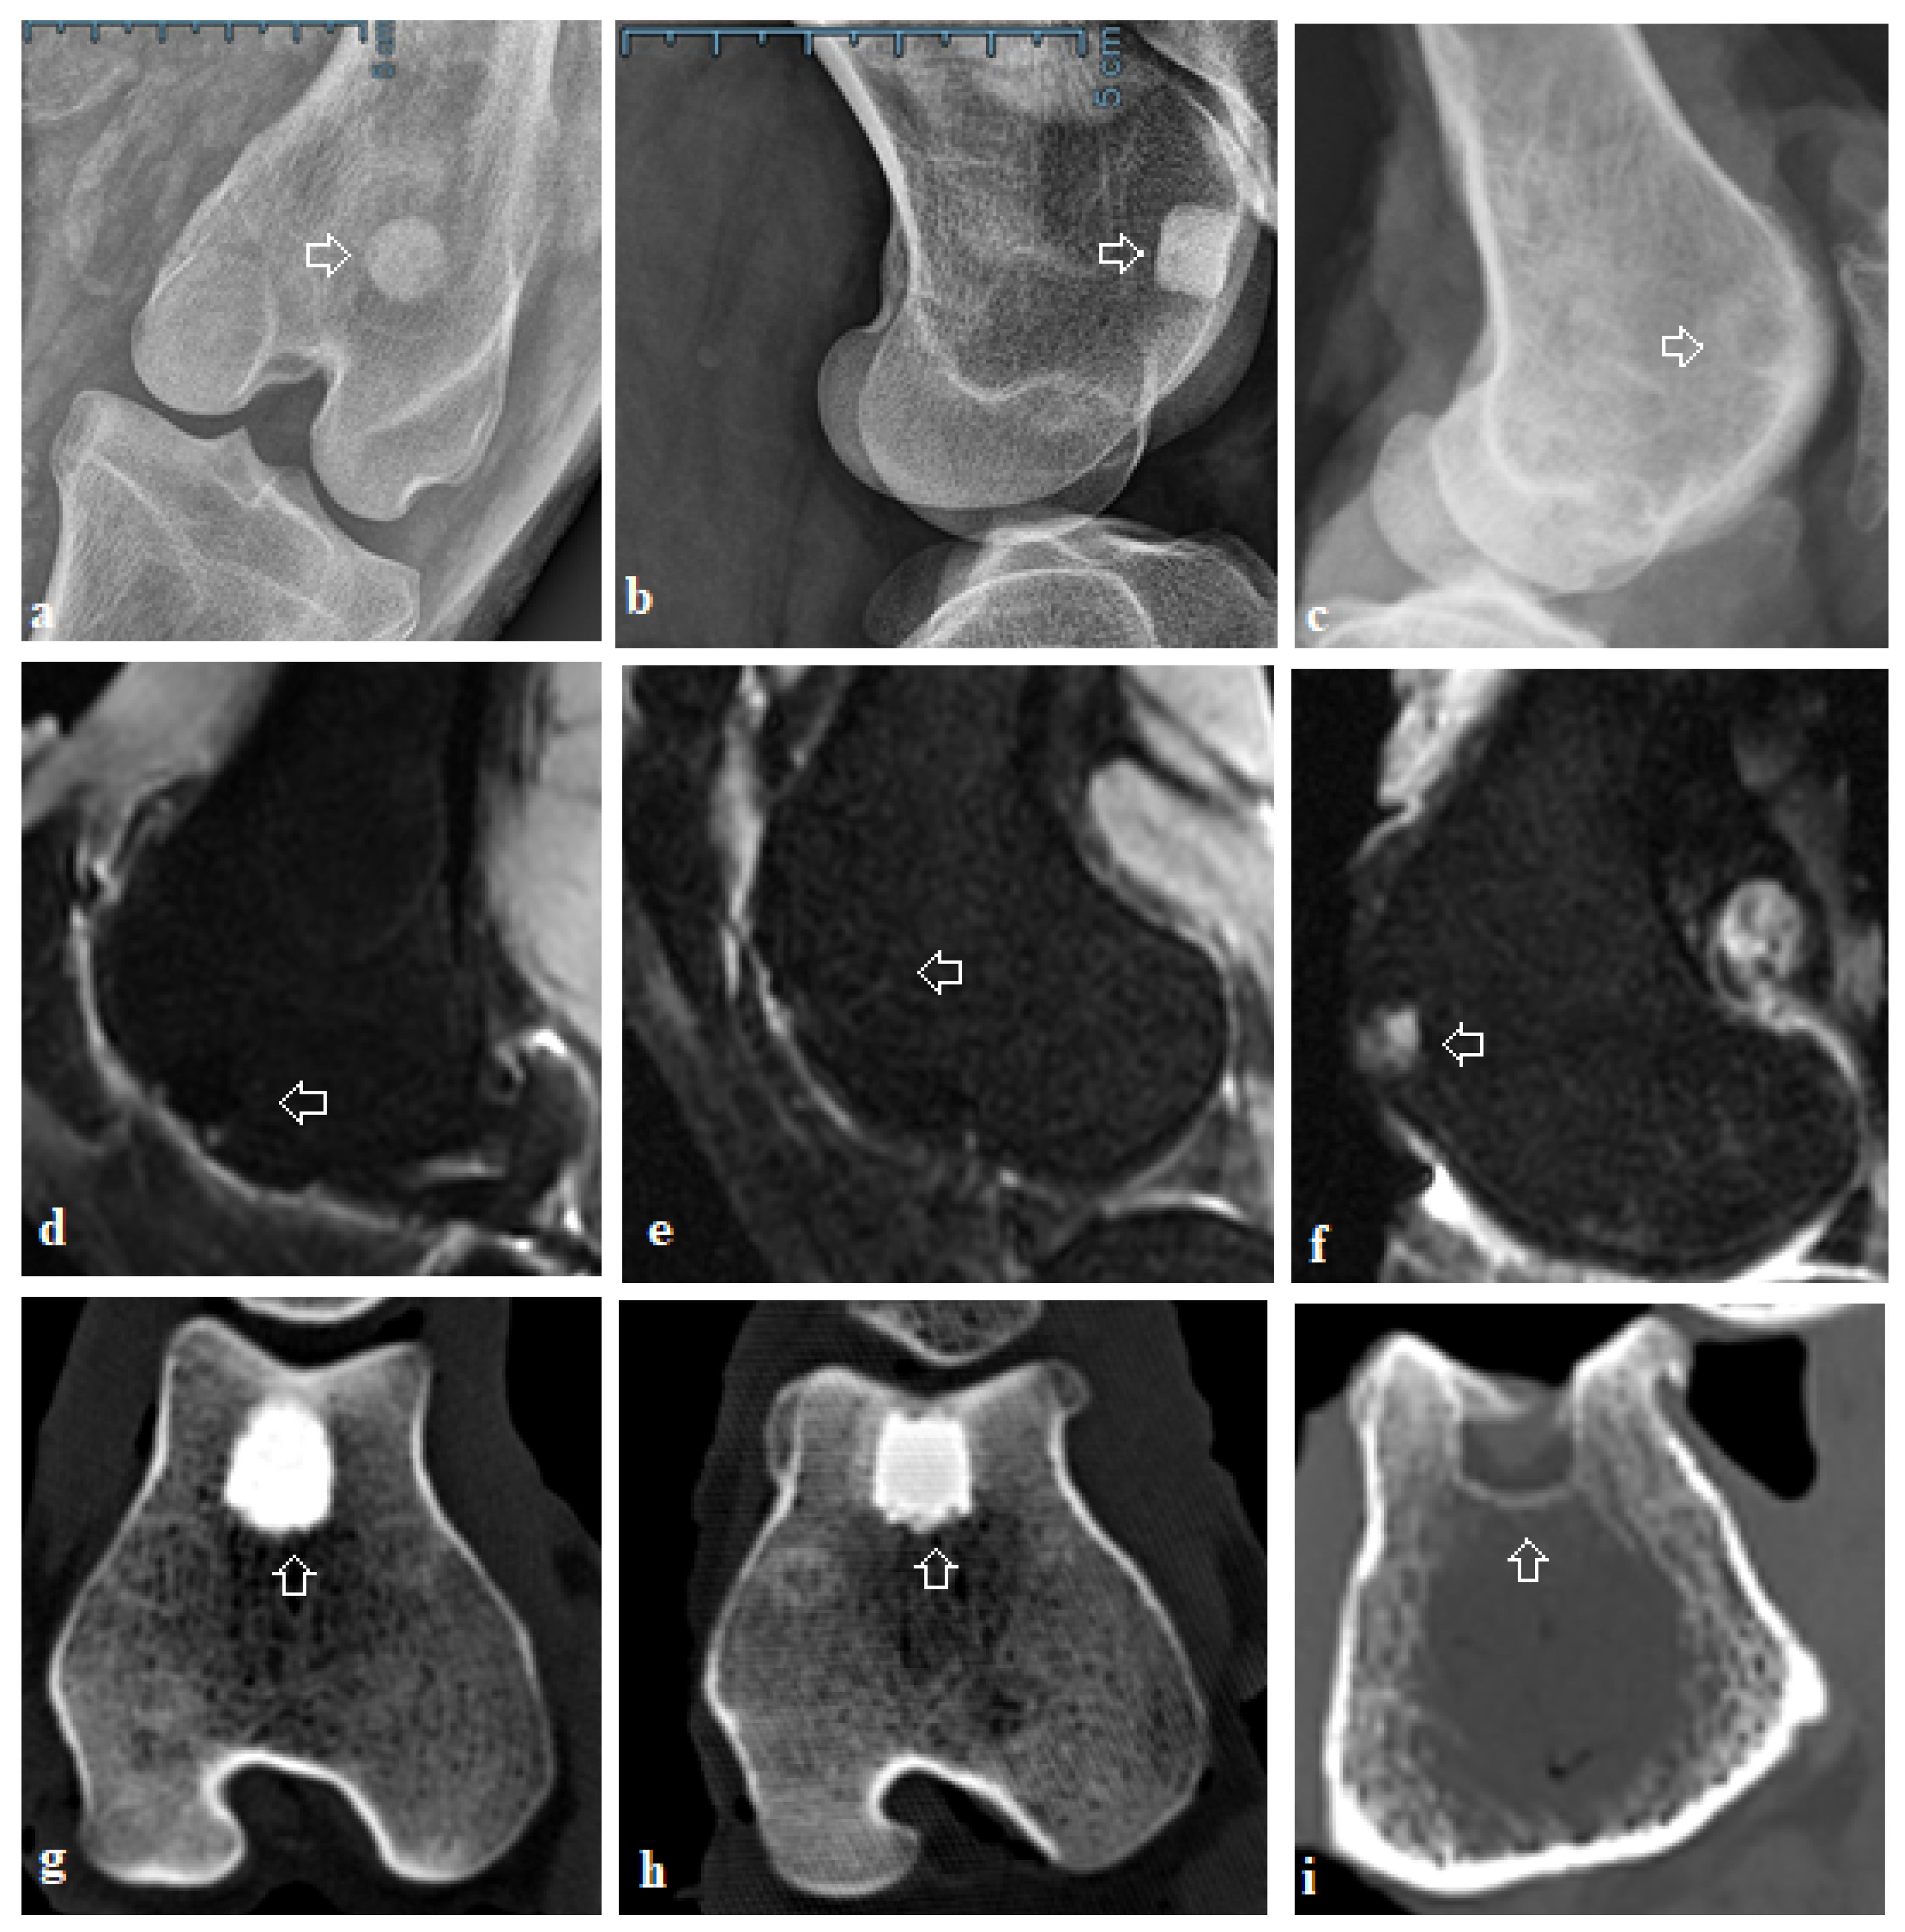

2.3. X-ray and Computed Tomography Assessment

2.4. Magnetic Resonance Imaging